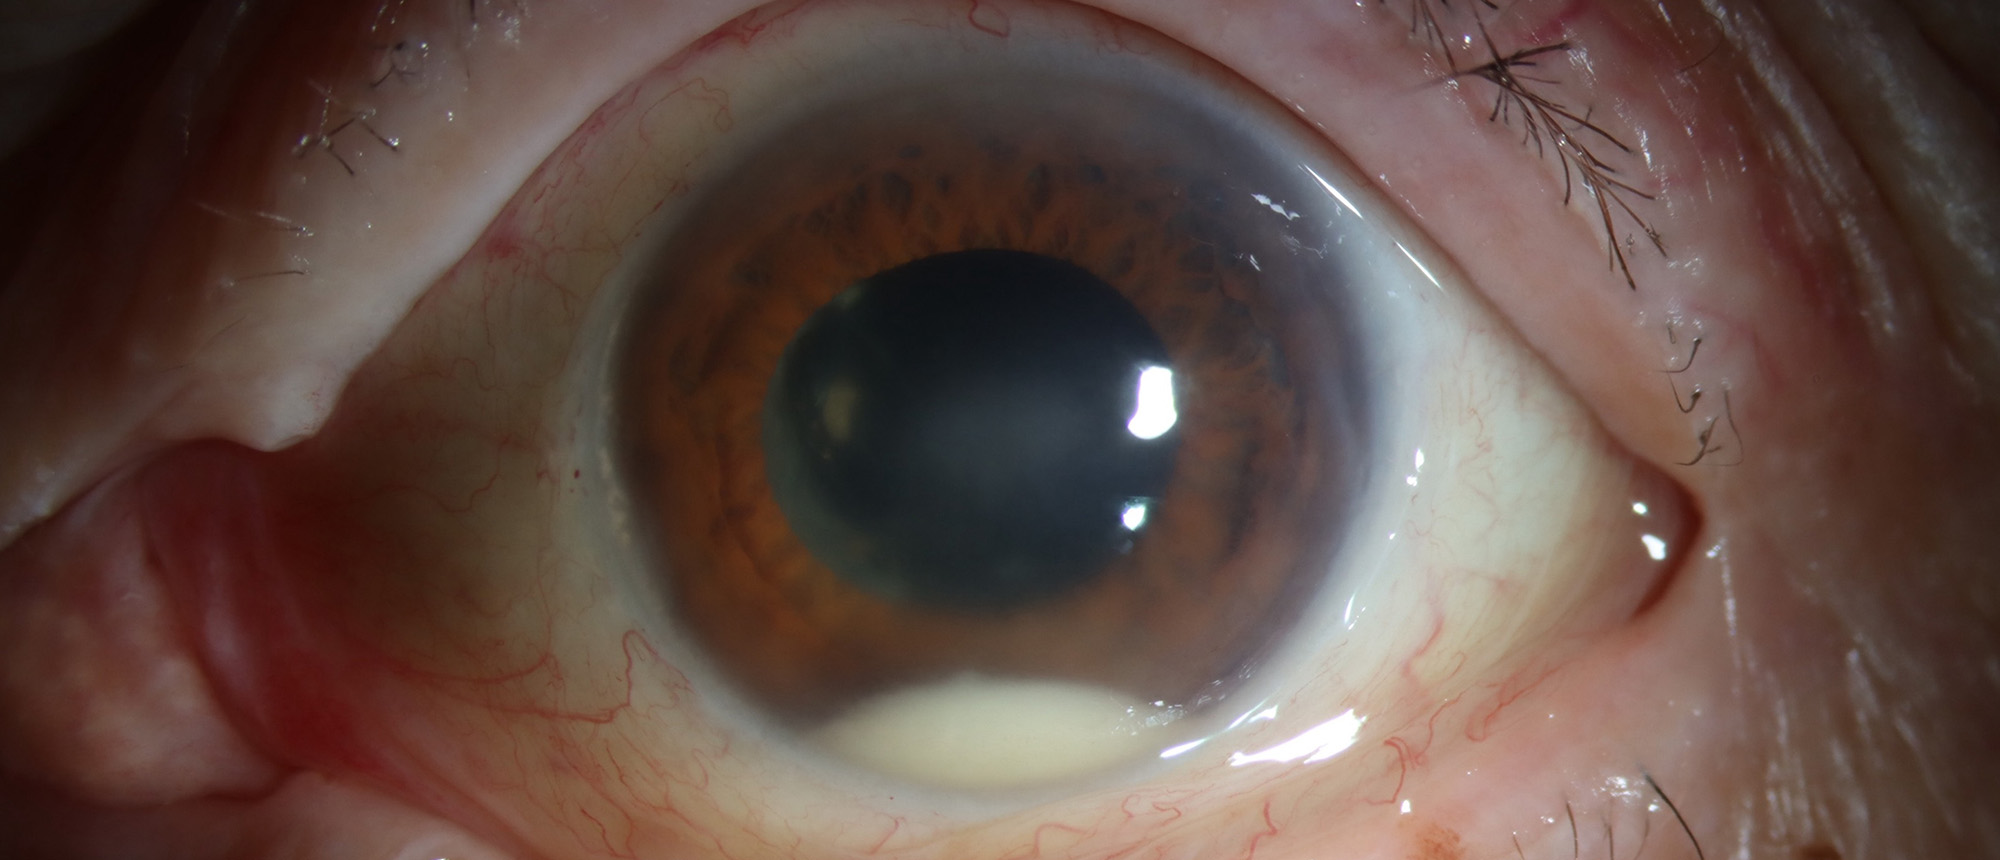

Corneal Edema and Secondary Angle Closure Glaucoma Due to Cosmetic Iris Implants Cosmetic iris implants have gained significant popularity in the media in the past 20 years. Despite their appeal to thousands of individuals across the globe, these implants have vision-threatening consequences. This …